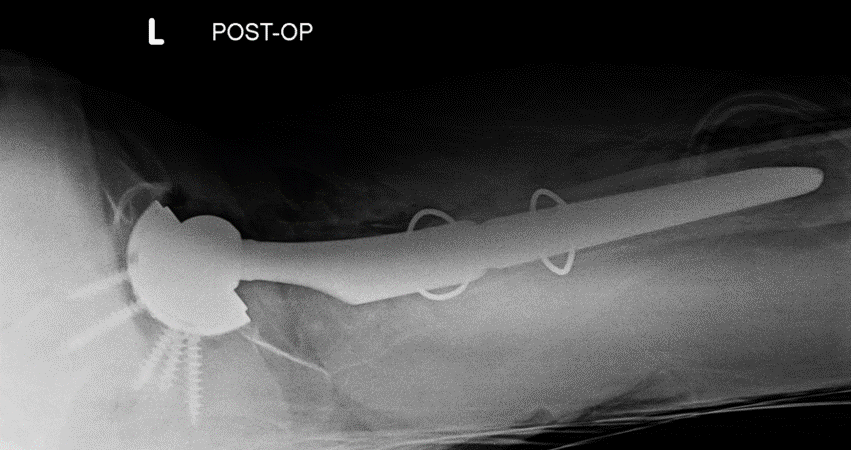

Case: 61 yo F w/ painful right revision TKA after a fall. Elevated serum Co, Cr. Not infected. Treatment of the femur? Management of well-fixed TM tibial cone?

5

Signficant metallosis in the joint and osteolysis about the femoral condyles. Cement-in-cement revision to DFR with retention of well-fixed TM tibial cone. Data on outcomes of retained, well-fixed cones coming in 2023!

2